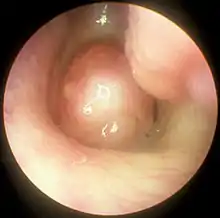

| A nasal polyp | |

Nasal polyps can be seen on physical examination inside of the nose and are often detected during the evaluation of symptoms. On examination, a polyp will appear as a visible mass in the nostril.[5] Some polyps may be seen with anterior rhinoscopy (looking in the nose with a nasal speculum and a light), but frequently, they are farther back in the nose and must be seen by nasal endoscopy.[12] Nasal endoscopy involves passing a small, rigid camera with a light source into the nose. An image is projected onto a screen in the office so the doctor can examine the nasal passages and sinuses in greater detail. The procedure is not generally painful, but the person can be given a spray decongestant and local anesthetic to minimize discomfort.[13]